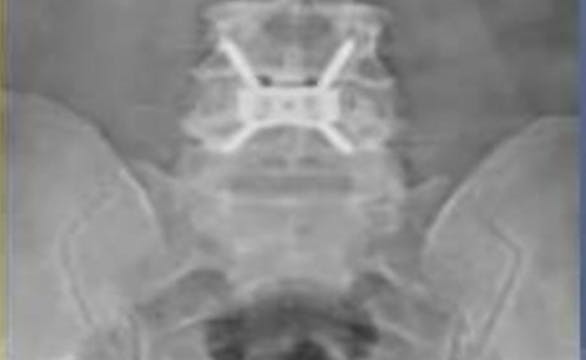

Direct screw fixation of spondylolysis without fusion

This video shows a interbody fusion L4/5 with a standalone intervertebral cage consisting of a titanium plate compound which is fixed with four screws ...